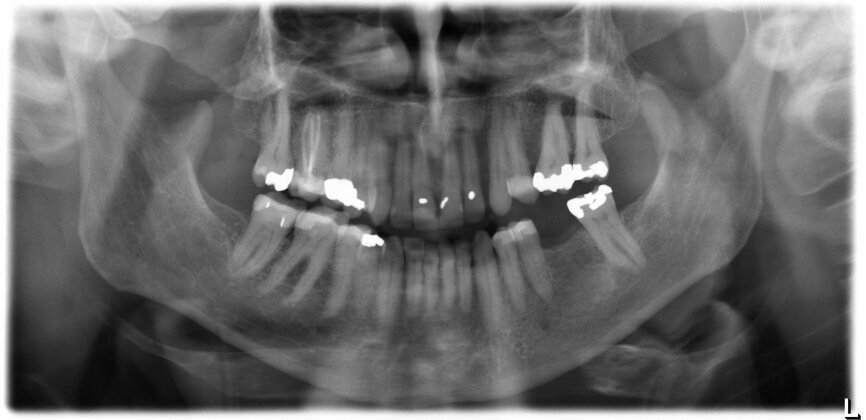

The patient, a 67-year-old non-smoking man without any relevant medical history, was referred to the office with a missing tooth (#36) due to persistent apical periodontitis. The tooth had been extracted more than one year prior to the procedure and the molar site was well maintained and fully healed (Fig. 1). A CBCT scan showed that the patient had favourable bone availability (Fig. 2), on which basis a one-stage placement of a 5.5 × 10.0 mm Straumann BLX implant was planned. After surgically installing the implant (Figs. 3–7), Salvesen allowed the surrounding soft tissue to mature and heal for six weeks (Fig. 8). He then removed the healing abutment to begin the prosthetic procedures for a temporary crown (Figs. 9 & 10). A stone master cast was made in the laboratory, and a temporary screw-retained PMMA crown was manufactured over a Straumann wide base temporary abutment for the crown (Fig. 11) and placed on to the implant (Figs. 12–14).

Fig. 1: Panoramic radiograph confirming the well-maintained anatomical conditions one year after tooth extraction.